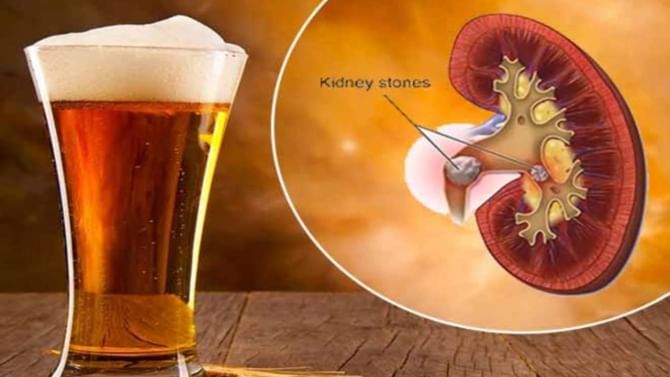

ಬಿಯರ್ ಕುಡಿಯುವುದರಿಂದ ಕಿಡ್ನಿ ಕಲ್ಲು ಸಮಸ್ಯೆಯಿಂದ ಮುಕ್ತಿ ಹೊಂದಬಹುದೇ?

Beer Consumption: ಬಿಯರ್ ಕುಡಿಯುವುದರಿಂದ ಕಿಡ್ನಿ ಸ್ಟೋನ್ ಗುಣವಾಗುತ್ತಾ? ಇದು ಎಷ್ಟು ನಿಜ